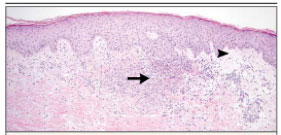

Yatışı yapılan hastaya viral enfeksiyon şüphesiyle valasiklovir ve pnömoni ön tanısı ile sefepim başlandı. Hastanın ateşi devam etti, döküntü kollara ve bacaklara yayıldı, kuru öksürük başladı. Kan, idrar ve cilt vezikül kültürlerinde üreme olmadı. VZV, HSV polimeraz zincir reaksiyonu (PZR) testleri negatif, CMV PZR 945 kopya/ml idi. HIV, EBV serolojik tetkikler negatifti. Cryptococcus antijeni, Lyme hastalığı için antikorlar, toksoplazma IgM-IgG negatifti. Galaktomannan ve interferon-gamma salınım testi (IGRA) negatif olarak belirlendi. CRP:102.3 mg/l (<5) idi. Cilt biyopsisi, hafif papiller dermal ödem ve nötrofilden baskın diffüz interstisyel dermatit olarak raporlandı.

Resim 3. Cilt biyopsisi patoloji preparatı